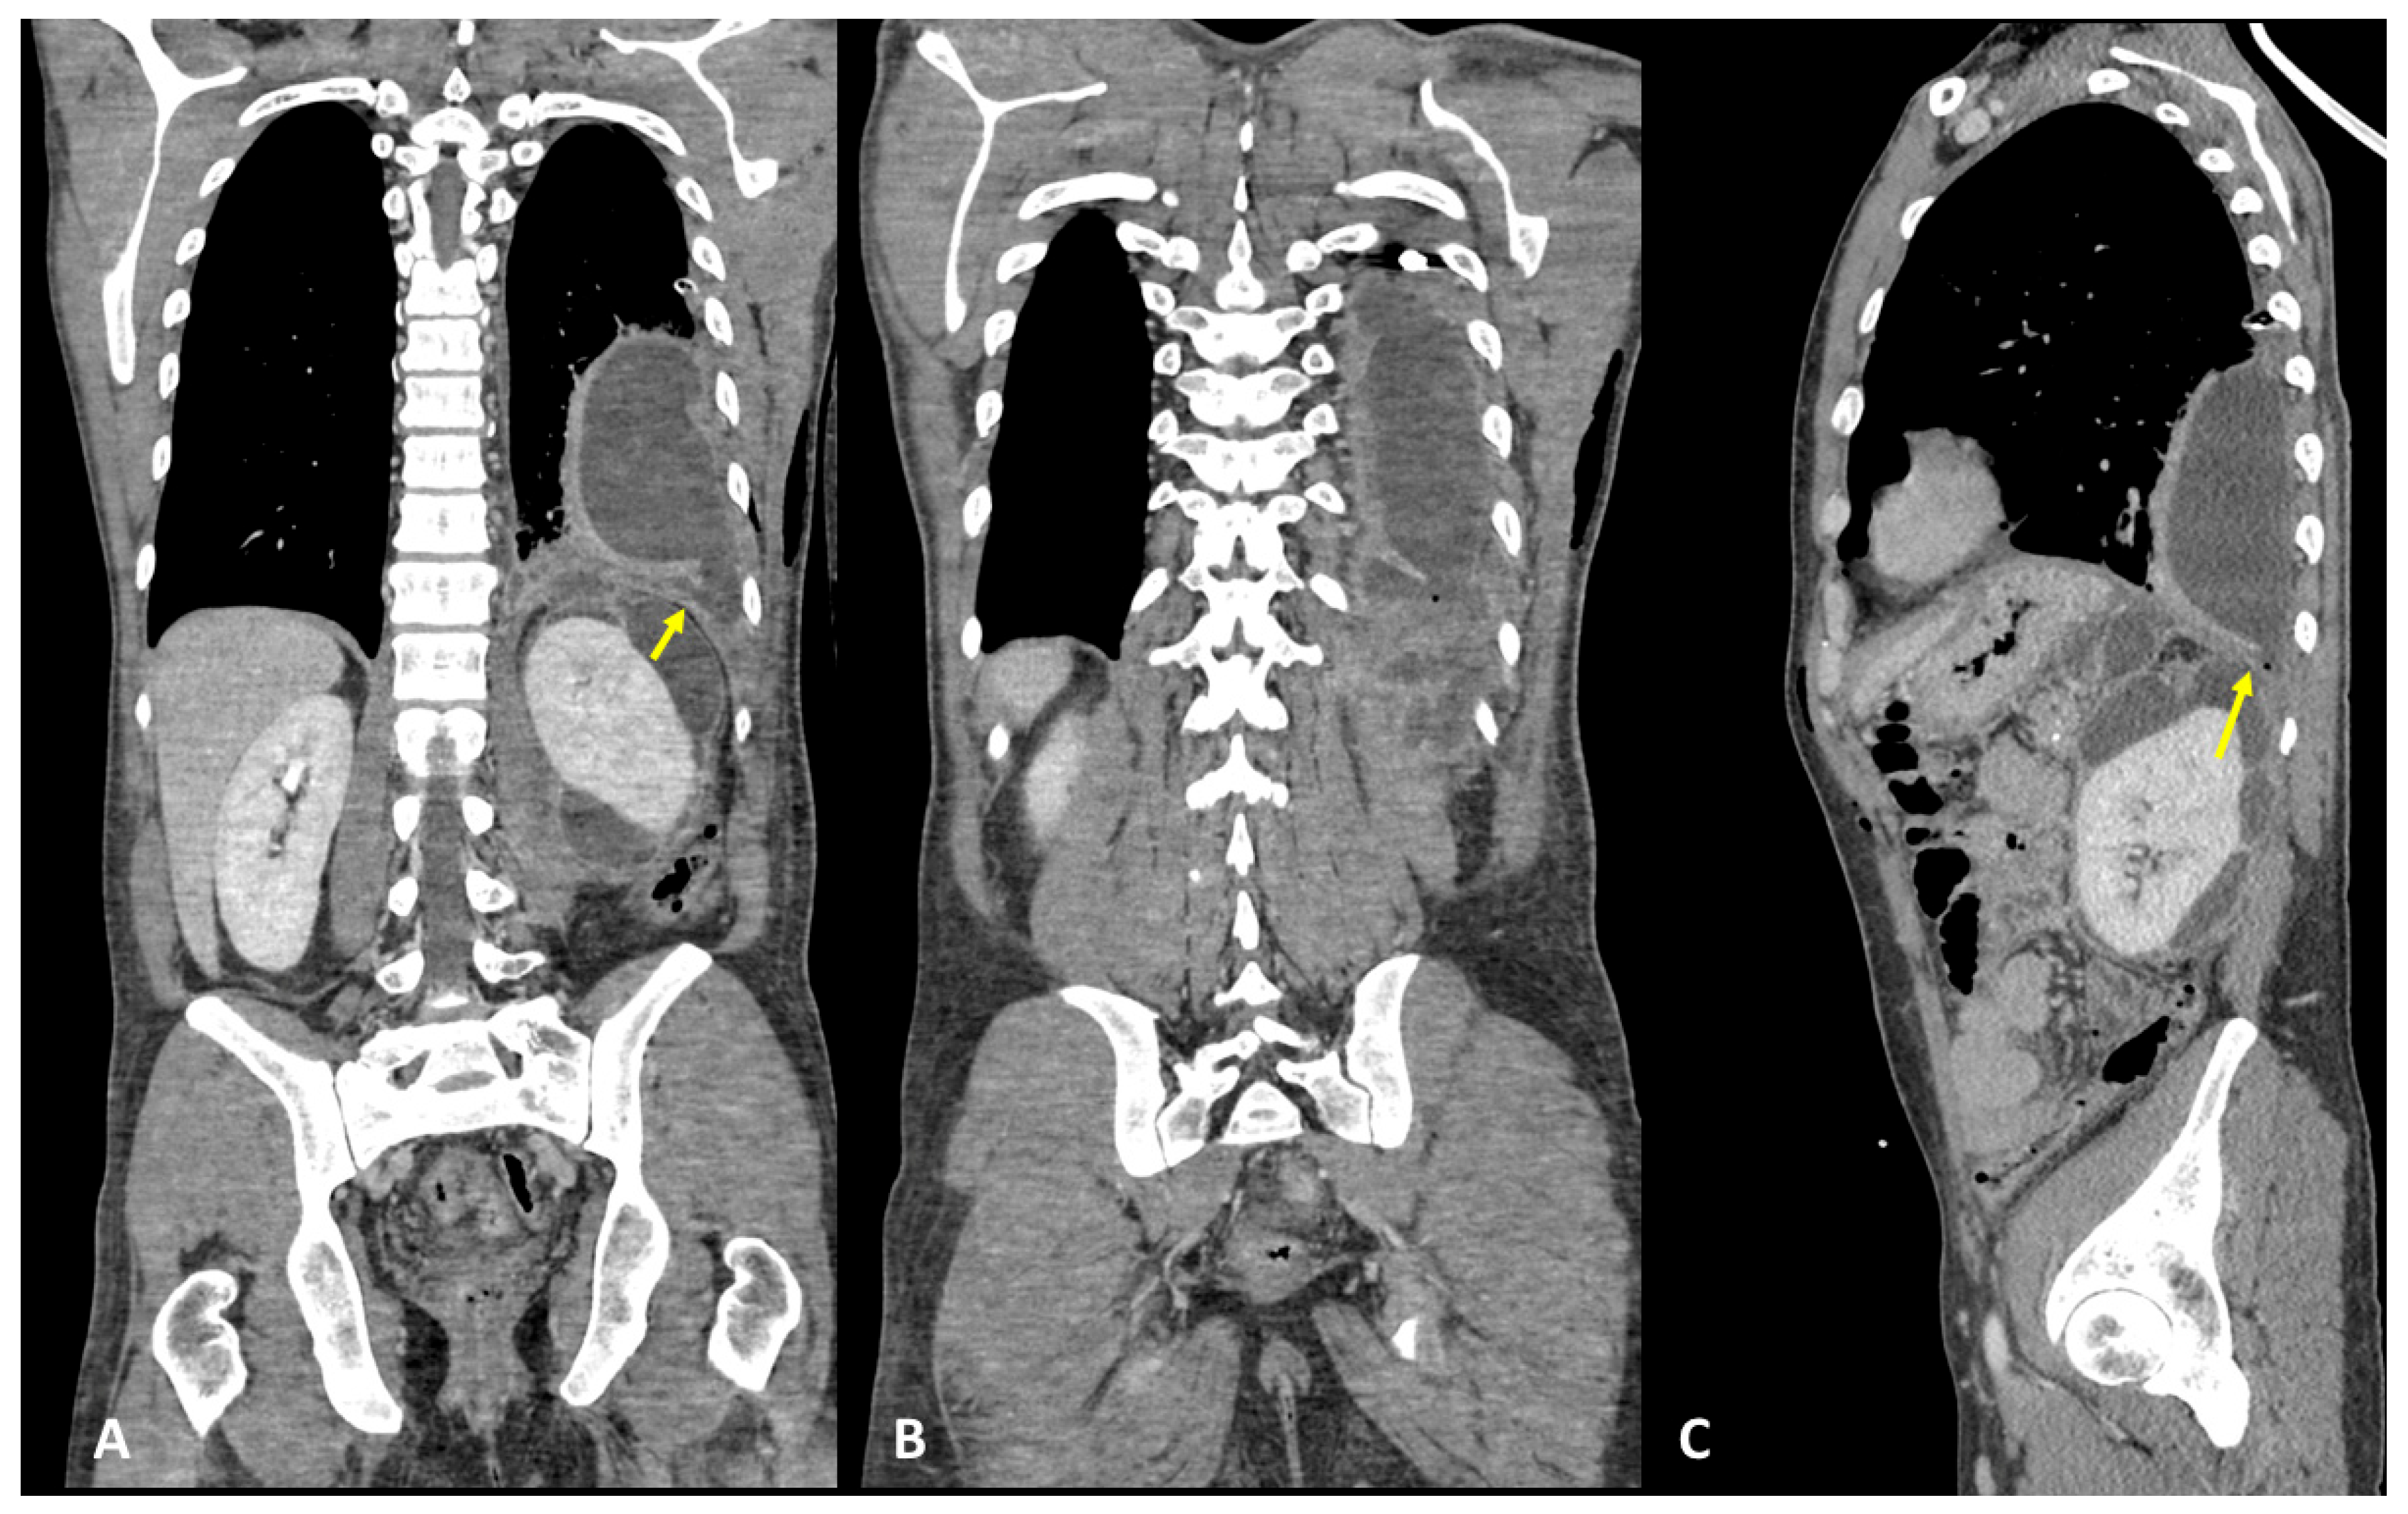

A 31-year-old woman, with a history of a previous splenectomy performed 10 years ago, was referred to an ER setting with fever and diffuse thoraco-abdominal pain and was not responding to 15-day antibiotic therapy. Physical examination revealed upper intense abdominal pain and diminished breath sounds over the left hemithorax. Laboratory routine tests showed mild neutrophilia, increased CRP, and severe increase in lipase and amylase levels, notably pancreatic amylase. The patient underwent chest X-ray that showed a PNX on the left side with left lower lobe parenchymal consolidation. The pneumothorax was drained. Subsequently, the patient underwent contrast-enhanced thoraco-abdominal CT confirming left pneumothorax, left pleural empyema, and multiple communicating large pancreatic pseudocysts, with a fistulous tract through the left diaphragm (Figure 7A–C). Therefore, a diagnosis of PPF was suspected, and contrast-enhanced MRI confirmed the same findings (Figure 8A,B). The patient immediately underwent drainage of the abdominal collections and pseudocysts located in the pancreatic tail and left subdiaphragmatic lodge. Antibiotic therapy was started. In the following days, the patient underwent surgery to evacuate the empyema, pneumolysis, and placement of double pleural drainage, as well as closure of the transdiaphragmatic fistula.

Figure 7.

(A–C) Contrast-enhanced CT and coronal (A,B) and sagittal planes (C) show left pleural empyema with gas bubbles and multiple pancreatic pseudocysts located between the diaphragm, the pancreas tail, and the left kidney. A definite fistulous tract is seen (arrows).

Figure 8.

(A,B) Contrast-enhanced MRI, coronal planes, and CE T1- (A) and T2-weighted sequences (B) (same patient as Figure 7). MRI confirmed a left pleural empyema and multiple pancreatic pseudocysts located between the diaphragm, the pancreas tail, and the left kidney. The fistulous tract was detected (arrows).